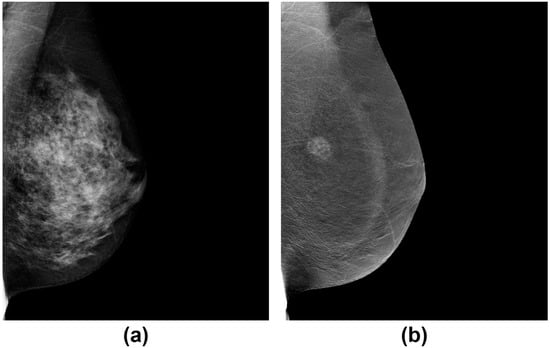

Figure 2.

An example of a mammographically occult mass in a dense breast (a) on the low-energy image but is demonstrated on the dual-energy recombined contrast-enhanced image (b) (CESM).

In recent years, the development and clinical implementation of contrast-enhanced spectral mammography (CESM) have shown considerable promise in therapy monitoring. CESM combines iodine-based intravenous contrast agents with dual-energy (low at 24–35 kVp and high 40–47 kVp) [] image acquisition to capture morphologic and microvessel density (MVD) features of the breast []. The resulting dual-energy recombined image has high sensitivity for detecting lesions in dense breasts that are otherwise occult on conventional mammography [] (Figure 2) []. More recent studies of CESM in monitoring breast cancer treatment response have shown that CESM measured tumor size at pre- and during treatment time points is highly correlated to MRI [,] with comparable sensitivity and specificity to predict treatment response. However, CESM is not without limitations. Given the need of iodine-based contrast agents for the exam, there is a risk of adverse reactions in some patients. False positives in dealing with fibroadenomas, hamartomas, intra-mammary nodes, and fat necrosis have significantly reduced the specificity of this method as a primary technique for breast cancer. Since CESM and DBT are promising mammographic techniques that may potentially add values to treatment monitoring, studies in large patient populations will be important to validate the initial findings and to stratify imaging phenotypes by subtype.